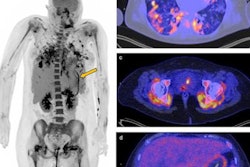

The study found that the F-18 FDG-PET/CT scans identified 36 sites of organ involvement among the eight patients in the cardiovascular subgroup, and 73 sites of organ involvement among the 38 patients in the non-cardiovascular subgroup.

Regarding cardiovascular manifestations, the PET/CT scans were used to identify lesions in the pericardium (2), coronary arteries (5), as well as aorta and other vessels (4). In descending order of frequency, the sites of involvement in the arteries were the abdominal aorta (3) and iliac arteries (3), followed by hepatic arteries, descending aorta, coeliac artery, renal artery, and right-sided mesenteric vessels (1 each).